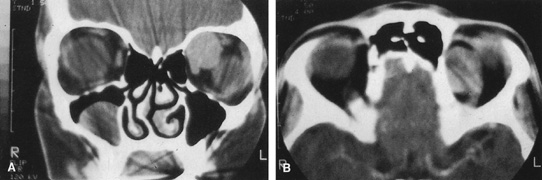

Valuable information about the nature and extent of an orbital pathologic process is provided by imaging studies such as computed tomography (CT) scan, magnetic resonance imaging (MRI), and orbital echography. Better spatial resolution, ready accessibility, and lower cost make CT the preferred choice for orbital imaging in most cases. Orbital fat provides a natural contrast between most adjacent orbital structures on CT scanning, and orbital bones are visualized well. Computed tomography is essential for evaluation of the orbital bones because they cannot be imaged with MRI. Direct coronal or sagittal images are important to identify the relationship of a lesion to the optic nerve so that the surgical approach can be planned to avoid traversing the optic nerve (Fig. 1).

Fig. 1. A. Axial CT scan demonstrating a large, well-encapsulated lesion in the orbital apex. Coronal (B) and sagittal (C) scans demonstrate that the mass lies inferior and medial to the optic nerve within the intraconal space. This information is useful in planning the surgical approach to the mass, which should avoid traversing the optic nerve.

Magnetic resonance imaging is useful in selected cases, especially when evaluating the orbital cranial junction. Significant bony artifact and a lack of orbital fat in the orbital apex make CT scan resolution of the orbital apex structures poor. Because cortical bone has low signal on MRI, there is no bone artifact when viewing the orbital apex on MRI. The lack of intervening fat in the apex to provide contrast is overcome on MRI because contrast is provided by the individual nuclear characteristics of each tissue so that the orbital apex structures are visualized well. Consequently, conditions that affect the optic nerve and chiasm, such as optic nerve meningioma and glioma, generally are evaluated with MRI rather than CT scan (Fig. 2).

Fig. 2. A. Axial orbital CT scan of right optic nerve meningioma. Note lack of detail in orbital apex. B. Axial orbital MR image, same patient. Note increased detail in orbital apex owing to lack of bone artifact. C. MRI with gadolinium contrast. Note extension into brain not easily appreciated with CT scanning or MRI without contrast.